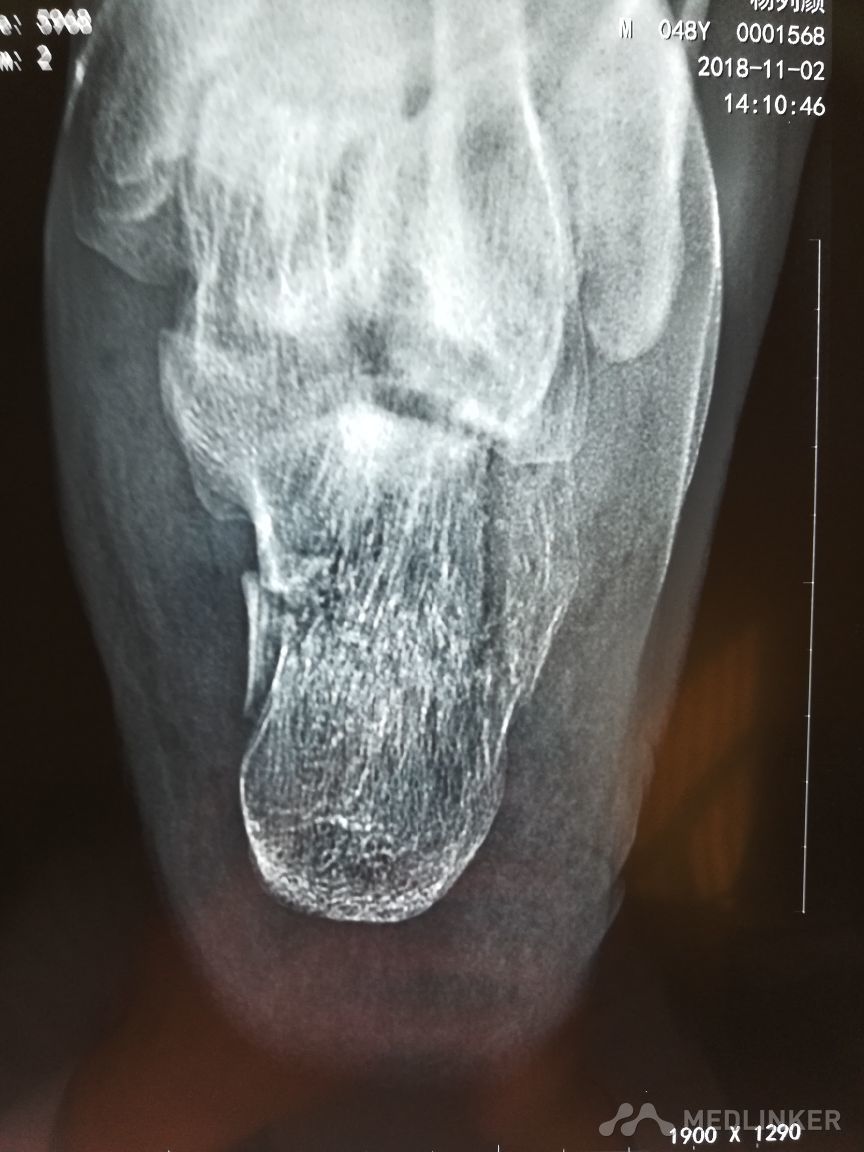

各位老师看看这个跟骨骨折需要手术吗

患者,男,48岁,2天前从高处摔下,伤及左足,拍片见左跟骨粉碎性骨折大家看看是否需要手术治疗,患者不大想手术